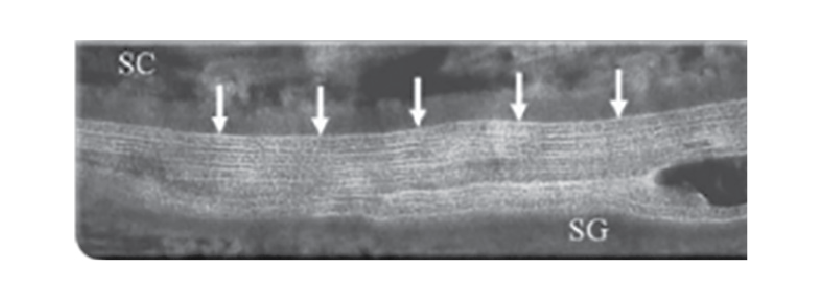

Елідел®відновлює шкірний бар’єр до показників нормальної здорової шкіри з формуванням нормального за структурою та суцільного біліпідного шару зовнішньої мембрани, на відміну від топічних кортикостероїдів7

Після лікування пімекролімусом:

утворення нормального за структурою та суцільного біліпідного шару зовнішньої мембрани7

SC – роговий шар SG – зернистий шар ТКС – топічні кортикостероїди

Трансмісійна електронна мікроскопія перехідної зони між зернистим і роговим шаром